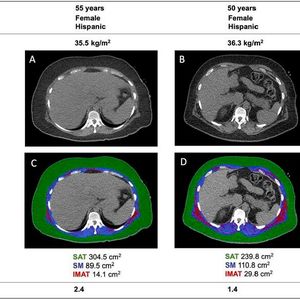

Researchers used CT scans to analyse each patient’s body composition, measuring the amounts and location of fat and muscle in a section of their torso.

(Source: Vivianty Taqueti/ European Heart Journal)

All the patients were tested with cardiac positron emission tomography/computed tomography (PET/CT) scanning to assess how well their hearts were functioning. Researchers also used CT scans to analyse each patient’s body composition, measuring the amounts and location of fat and muscle in a section of their torso.

To quantify the amount of fat stored within muscles, researchers calculated the ratio of intermuscular fat to total muscle plus fat, a measurement they called the fatty muscle fraction.